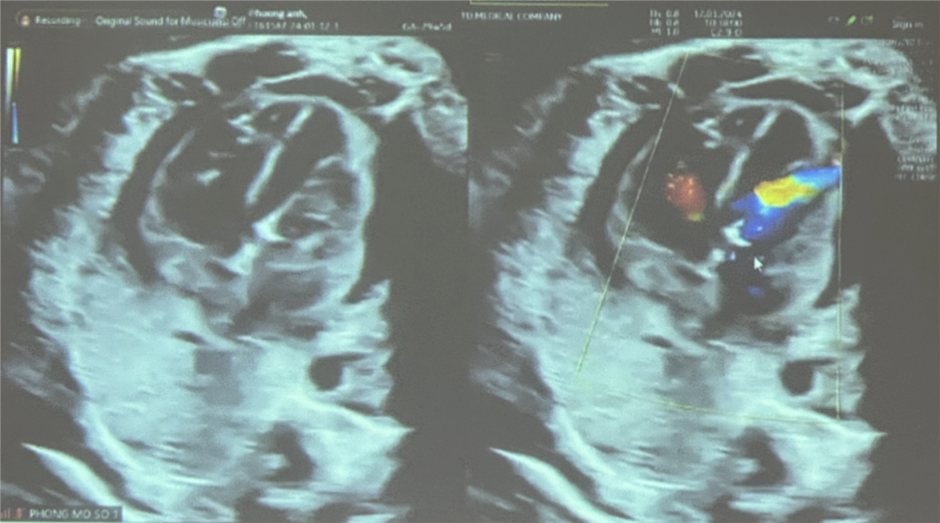

Kết quả siêu âm kiểm sau thực hiện thông tim can thiệp cho thai nhi

Trước đó, trong quá trình khám thai, chị A được phát hiện bào thai có bất thường về tim lúc thai 21 tuần với chẩn đoán là hẹp van động mạch chủ tiến triển. Thai phụ đã được tiến hành chọc ối xét nghiệm di truyền Array chưa bất thường. Ngày 11/1, thai nhi được 29 tuần với diễn tiến hẹp van động mạch chủ nặng, đường kính van 2.6 mm, vận tốc máu qua van động mạch chủ 300cm/giây, gây thiểu sản thất trái nặng hơn, trào ngược van 2 lá mức độ nặng.